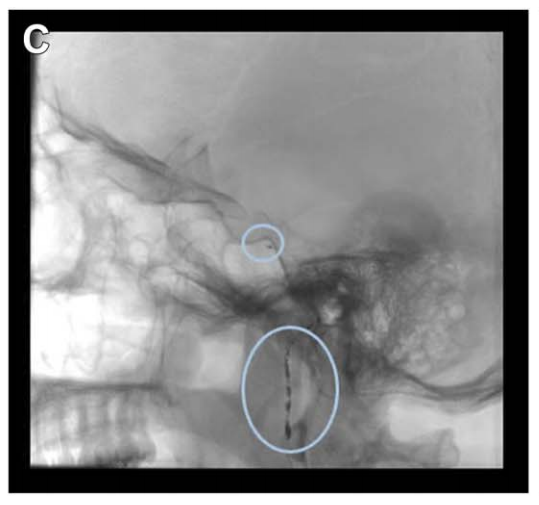

由于已知该肿瘤的血供丰富,福教授在手术前进行了DSA检查,显示其供血动脉主要为咽升动脉及脑膜垂体干。为降低后组颅神经损伤风险,选用弹簧圈栓塞。栓塞可减少出血、软化肿瘤,便于切除。

诺亚术前栓塞咽升动脉及脑膜垂体干